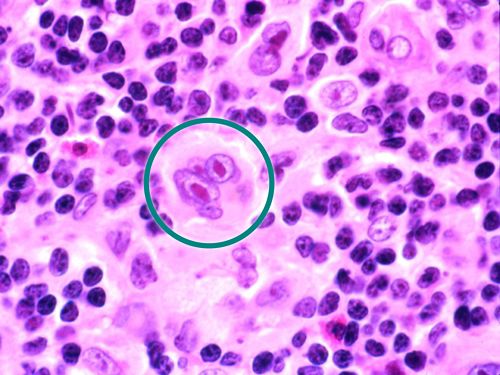

Микропрепараты: Лимфогранулематоз и Нодулярный Склероз

Раздел: Секреты мастерства